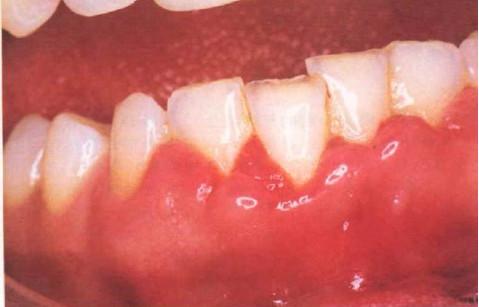

图片来自网络

上图可见前牙周围的牙龈都是光亮的状态,而且明显比后牙的牙龈肿胀。往往还伴随有口臭的症状。